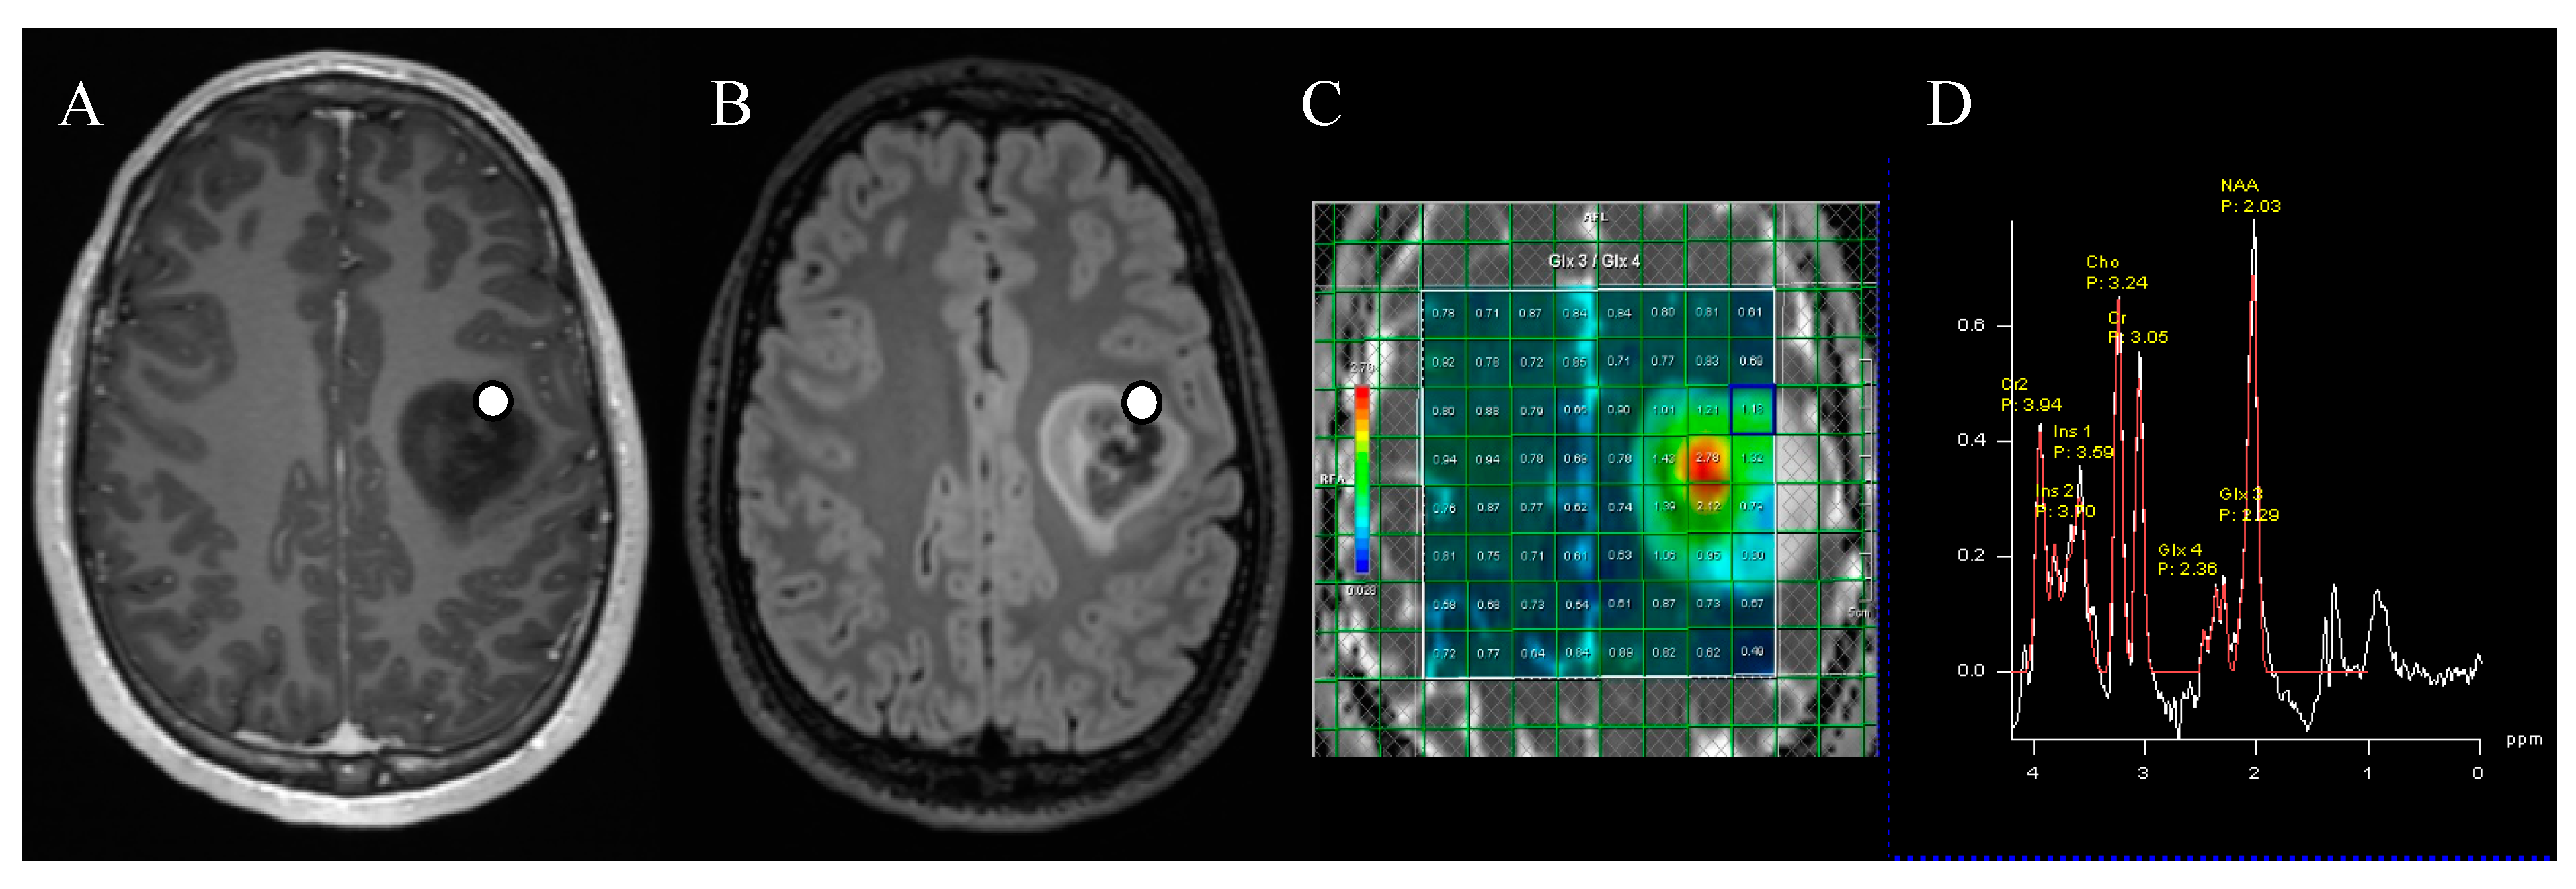

2.3. MR Spectroscopy Acquisition